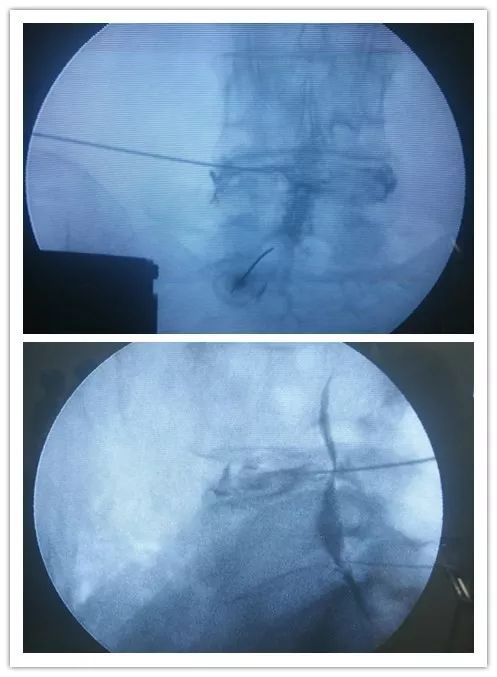

蒙自易康和医院“疼痛科”利用微创介入手术和物理治疗、中医传统疗法相互结合,解决顽固性疼痛(三叉神经痛、后枕部疼痛、慢性偏头痛)、脊柱源性疼痛(颈椎病、腰腿痛、颈椎间盘突出、腰椎间盘突出症)、神经性疼痛(带状疱疹后神经以及各种急慢性肌肉关节损伤)等在内的疼痛疾病,获得广大患者的认可。

我院运用国内外最先进的射频、孔镜治疗技术,为广大疼痛患者提供多元化有效的治疗方法。为众多受病痛折磨的患者解除了疼痛困扰,使她们重新回到了工作岗位、享受美好的生活。秉承“患者至上,团队协作”的理念,突出我科“微创介入治疗”,以精准和可视化为优势的特点。为广大患者提供一流的医疗服务。